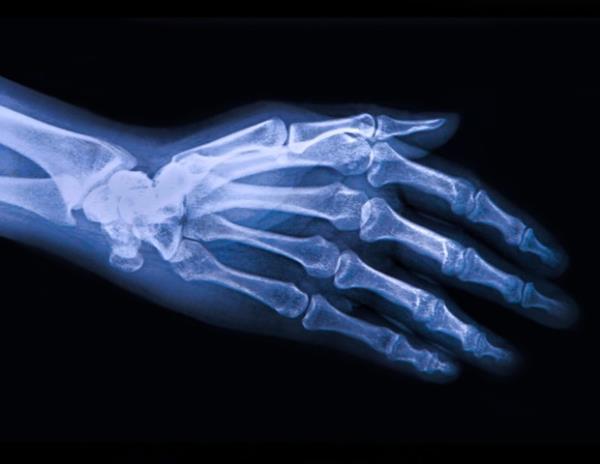

骨关节炎是世界范围内最常见的关节炎,并且在残疾和医疗保健利用方面具有日益增加的全球负担。它还与各种合并症有关,这种联系近年来得到了关注。在2023年更新的骨关节炎管理建议中,欧洲风湿病协会联盟(EULAR)认识到骨关节炎是一种严重的疾病,对个人和社会都有重要影响。然而,大多数骨关节炎患者并没有得到最佳的治疗。这代表了一个重要的未满足的需求-特别是考虑到其他系统性合并症。为了进一步探讨这一点,ComOA将病例对照和队列研究结合起来,对英国、荷兰、瑞典和西班牙的300多万人进行了初级保健。在维也纳举行的2024年EULAR大会上分享的分析研究了骨关节炎与首次骨关节炎诊断前后确定的61种不同合并症之间的关系。然后,研究人员测试了他们在四个国家的发现的相似性——如果所有中心的结果都是显著的,并且倾向于一个方向,那么一致性就被确定为存在。在这四个数据库中,有845,373例骨关节炎病例和2,556,243例对照。汇总的患病率数据显示,骨关节炎患者中有几种情况比对照组更常见。患病率最高的疾病是慢性背痛、高血压、过敏、白内障、眩晕、抑郁和糖尿病。在研究的33种合并症中,10种如纤维肌痛、多肌痛和慢性背痛在四个国家的诊断中显示出与骨关节炎相关的一致证据。诊断为骨关节炎后出现的三个主要合并症是纤维肌痛、类风湿关节炎和多肌痛。14种慢性疾病,包括心力衰竭、糖尿病、痴呆和慢性阻塞性肺疾病,在诊断骨关节炎之前或之后都没有发现与骨关节炎相关的一致证据。这些发现对于骨关节炎患者的规划管理具有重要意义,并表明需要进一步的研究来确定骨关节炎及其合并症之间的因果关系。